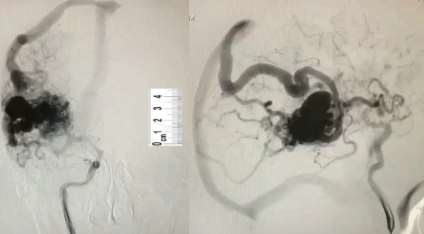

O paciente da questão anterior realizou uma angiografia.

Fonte da Imagem: cedida pelo autor

De acordo com o achado dessa imagem, assinale a alternativa CORRETA.